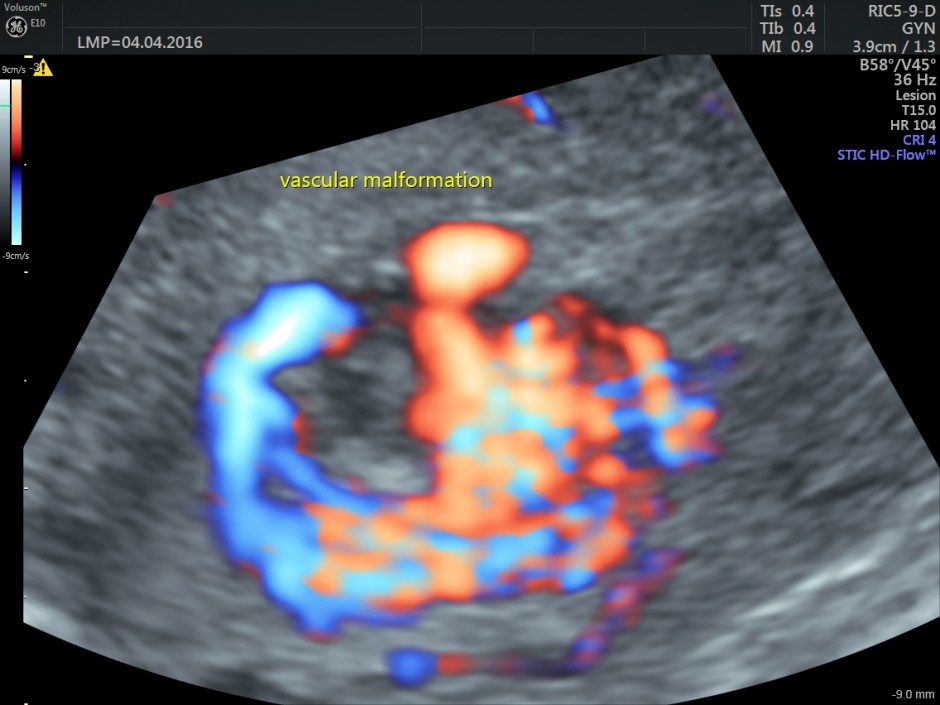

Colour and Power Doppler images are given below.

Increased vascularity is seen in the posterior aspect

Spectral Doppler images show arterial flow with low resistance at different points .

The following are the different sections of the Power Doppler reconstruction images of the trans-vaginal scan.

The following are the reconstructed 3D Power Doppler images.